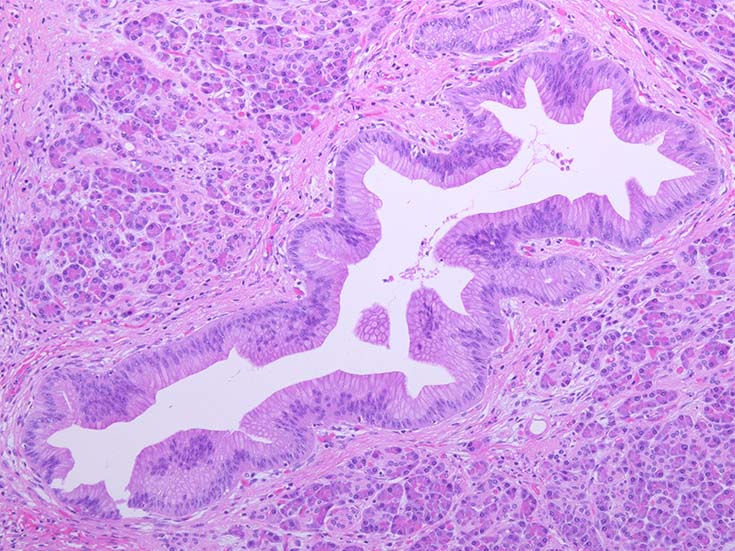

膵上皮内腫瘍性病変 pancreatic intraductal neoplasm(PanIN)*16

Low-grade PanINとhigh-grade PanINの分類

low-grade PanIN

high-grade PanIN

PanINの図譜はJohns Hopkins The Sol Goldman Pancreatic Cancer Research CenterのHome page*19から引用.

1. PanIN-1; PanIN発生の初期段階. 組織学的に, 核異型を伴わない, 核の極性が保たれている.

• telomereの短縮

• KRAS変異

• p16/CDKN2A変異

• Mucin(MUC)発現

2. PanIN-2, PanIN-3;

• TP53の不活化--PanINでのIHCでは機能喪失が,PanIN3のみで観察される. 膵癌発がん過程の遅い段階に出現する事象.

浸潤性膵癌では, 50-75%で不活化.

• SMAD4の不活化--PanIN3の30%で発現陰性化. PanIN-1,2では, SMAD4免疫染色は陽性. 発現の陰性化は後期PanINで発現する重要な異常*20.

浸潤性膵管癌では, 55%で不活化.